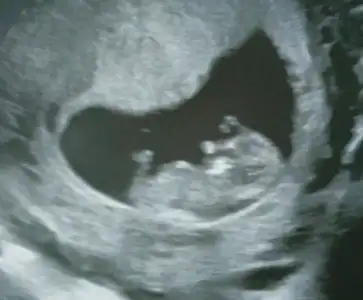

Kizlar Havalianne__ Havalianne__ bana da yorum yaparmisiniz ilki 6+4 haftalik

2cide ise 10+6 görüntüde altta da yaziyor. Her ikiside karindan bu arada